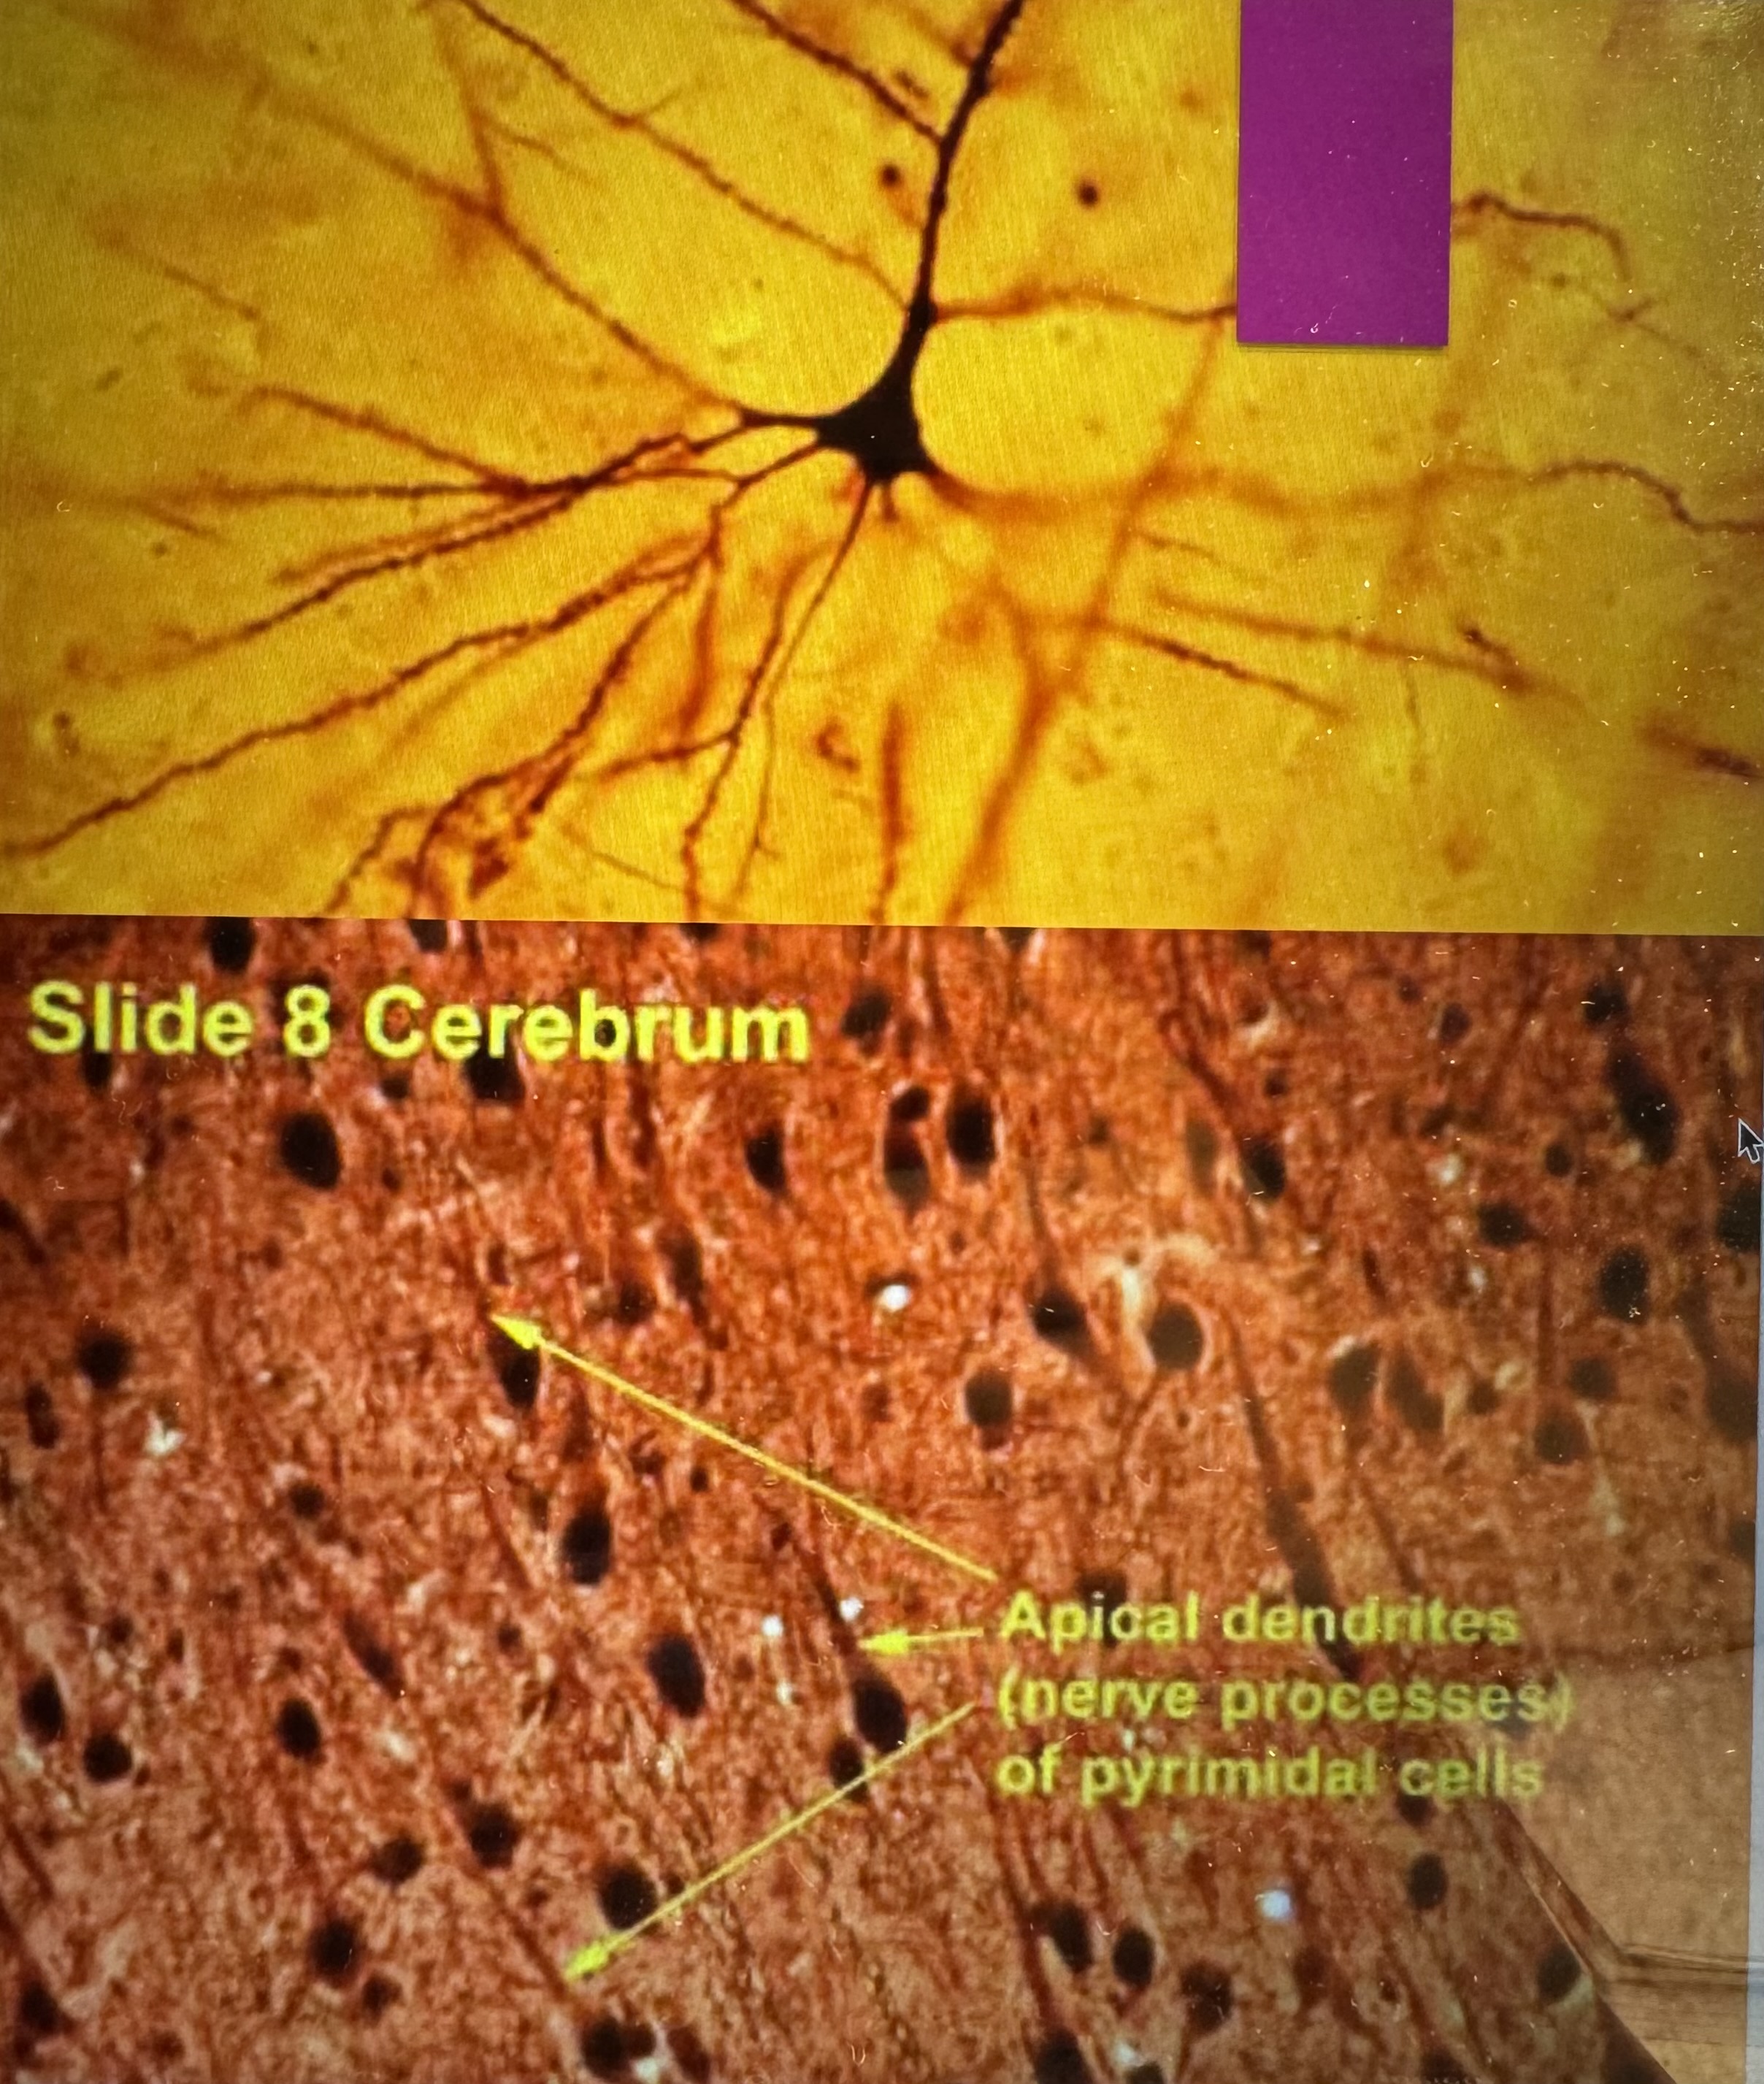

Neuron Histology